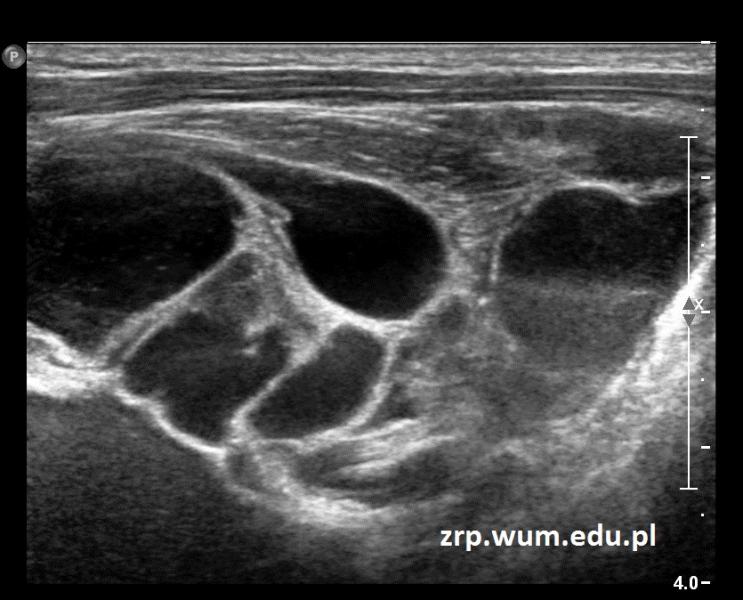

Przypadek 34: 5-letni chłopiec po złamaniu obojczyka prawego. Po zdjęciu gipsu w badaniu przedmiotowym wyczuwalny guz/torbiel w okolicy dołu podobojczykowego prawego.

Rozpoznanie: Kontrolne RTG nie wykazało zmian. W badaniu USG uwidoczniono wielokomorową zmianę torbielowatą, z przegrodami, o łącznych wymiarach ok.70x56x55mm; zmiana widoczna w dole pachowym prawym, sięga przedniej okolicy barkowej. Dwufazowa zawartość niektórych z komór zmiany.

Obraz USG odpowiada naczyniakowi limfatycznemu. Zmiana najpewniej była obecna już wcześniej, uległa powiększeniu po urazie.